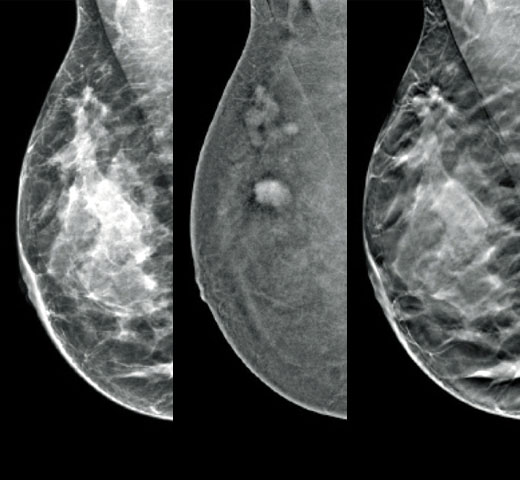

Screening & Diagnosis